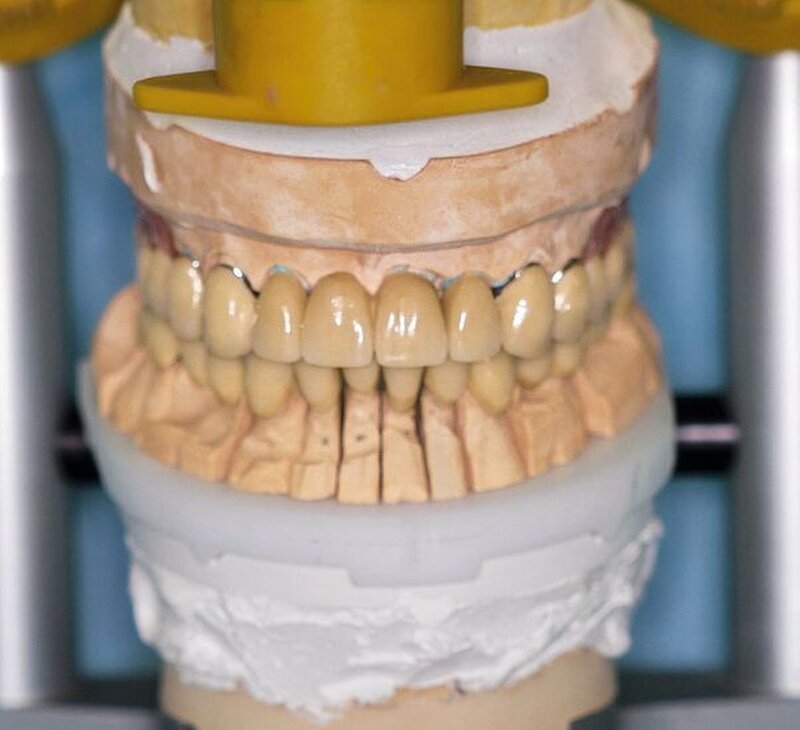

Die Abformungen des OK und des UK erfolgten als Korrekturabformung unter Verwendung eines A-Silikons. Zur Darstellung der subgingival liegenden Präparationsgrenzen wurden mit Adstringentien getränkte, geflochtene Retraktionsfäden in die Sulci aller Zähne eingelegt. Eine adäquate Trocknung der abzuformenden Bereiche wurde durch die Verwendung von Kompressions-Wattekappen, die auf den einzelnen Zähnen platziert wurden, durch Parotispflaster sowie durch eine konstante Absaugung erreicht. Um ein möglichst langes Verarbeitungsintervall zu erzielen, wurde das verwendete Silikon zuvor im Kühlschrank gelagert [Wöstmann et al., 1992; Wöstmann et al., 1999]. Nach erfolgter Abformung wurde ein Gesichtsbogen zur individuellen Übertragung des Oberkiefermodells in den Artikulator angelegt, danach wurden die Provisorien des I- und IV-Quadranten wieder befestigt. Nun wurden partielle interokklusale Registratschlüssel mithilfe eines intraoral anwendbaren Autopolymerisats im Bereich des II- und III-Quadranten angefertigt und beschliffen. In einem zweiten Schritt wurden die Provisorien im I- und IV-Quadranten entfernt und die partiellen interokklusalen Registratschlüssel des II- und III-Quadranten eingesetzt. In dieser Position wurden nun ebenfalls Registratschlüssel im I- und IV-Quadranten angefertigt und beschliffen. Durch dieses Vorgehen war es möglich, die im Rahmen der Registration ermittelte Position – unter Einbeziehung der präparierten Zahnhartsubstanz – auf die Modellsituation des Arbeitsmodells zu übertragen. Abschließend erfolgte die Farbauswahl. Die Arbeitsmodelle wurden mithilfe des zuvor angelegten Gesichtsbogens und der erstellten Registratschlüssel in einen teiljustierbaren Artikulator übertragen. Im Labor erfolgte die Herstellung der Nichtedelmetall-Gerüste der Einzelkronen 22, 32, 31, 41 und 42, die der Brücken 12 bis 21, 35 bis 37 und 43 bis 46 sowie die der Nichtedelmetall- Primärkronen 13, 14, 23 und 24.

Nach durchgeführter Verblendung und Anfertigung des Sekundärgerüsts der partiellen oberen Prothese sowie Anfertigung einer separaten Wachsaufstellung wurden die Kronen und Brücken erneut anprobiert, um etwaige Änderungen die Farbe der Restaurationen betreffend vor dem Glasurbrand durchführen zu können. Zudem wurde die Sekundärkonstruktion der partiellen oberen Prothese auf ihre Passgenauigkeit hin überprüft. In einem letzten Schritt erfolgte dann die Beurteilung der Okklusion der Wachsaufstellung in Relation zu den angefertigten Kronen und Brücken.